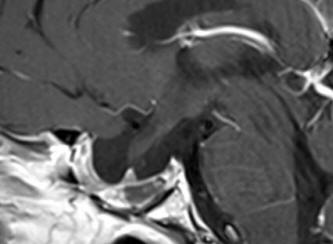

Fig-3: The next intraoperative MRI showing total resection of the mass and floating venous structures with deformed choroidal veins.

Fig-4: Saggital and coronal views showing the external drain  and  a clot over the mesencephalon.

Fig-7: The hematoma in the bed of resected tumor. Notice that there is no arterial spasm.